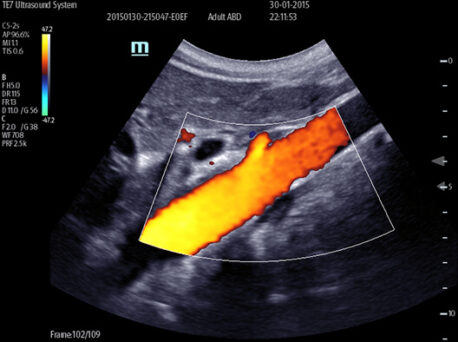

Smart Track

Dzięki zastosowaniu inteligentnego wykrywania naczyń krwionośnych, aparat może automatycznie optymalizować obraz Kolorowego i Power Dopplera oraz położenie bramki i spektrum Dopplera PW, żeby zredukować powtarzalne i czasochłonne działania i uprościć badanie naczyń krwionośnych